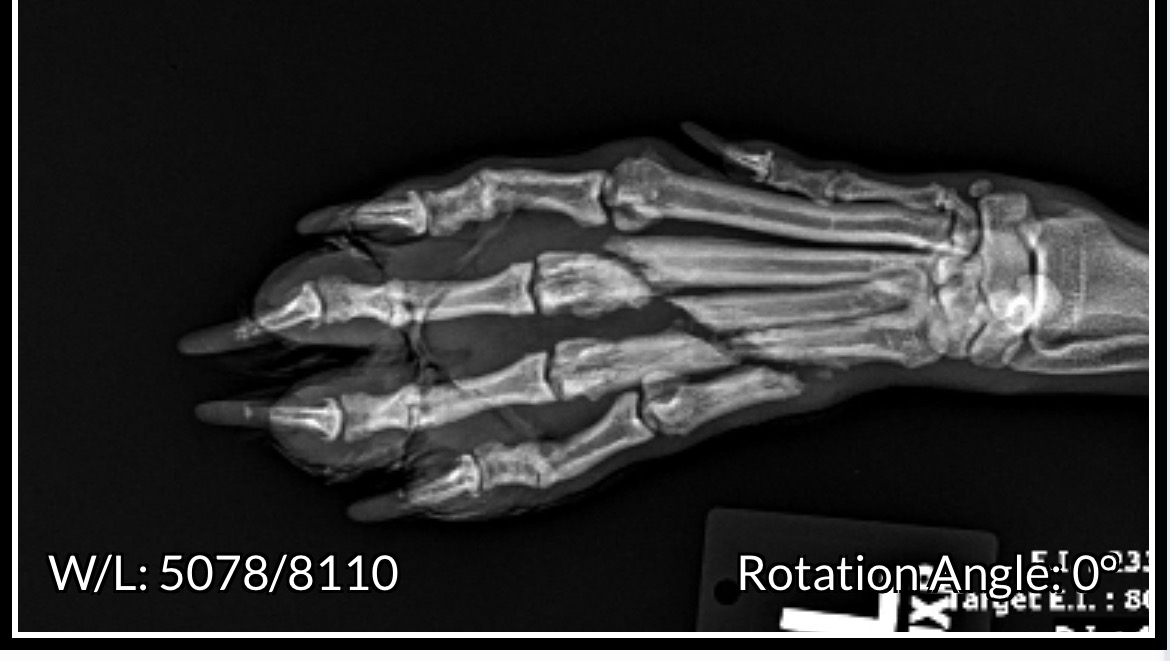

A week before we were driving from Mexico to Canada Foxy fell 25’ and we thought she was dead. She miraculously survived and only had a broken leg.

The vet put it in a cast and said it needed to be looked at in 2 weeks.

Yesterday the vet in Canada said the only way to keep Foxys leg is with surgery which is $7000. The toes aren’t lining up. We could amputate it but because it’s the front leg it isn’t ideal.